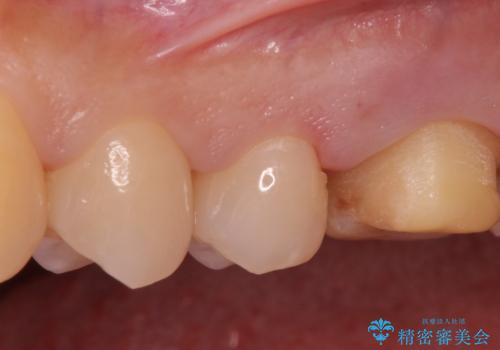

- 銀が目立つので白くしたいとの事で来院。

銀の詰め物を拡大鏡下で取り除き、う蝕がないことを確認してから

ZrCrの被せ物で治療を行いました。

また、一つ手前の歯に小さな虫歯があったため

e-maxインレーでの治療を行いました。